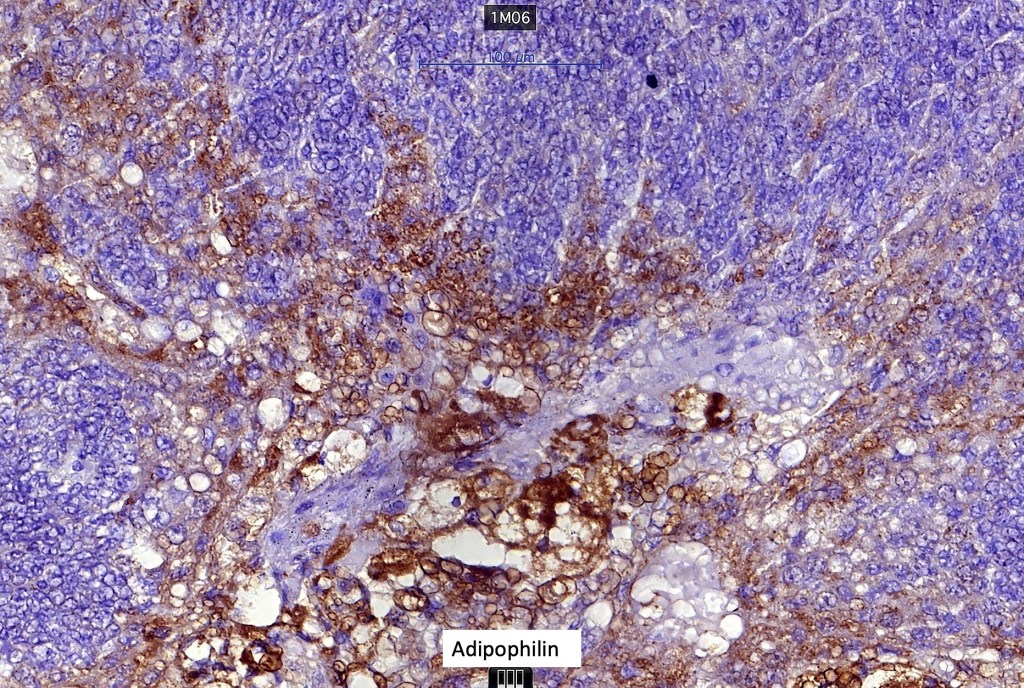

Immunohistochemistry (from the Muir-Torre patient except for EMA which was shared by Dr. Tsheri Dorji